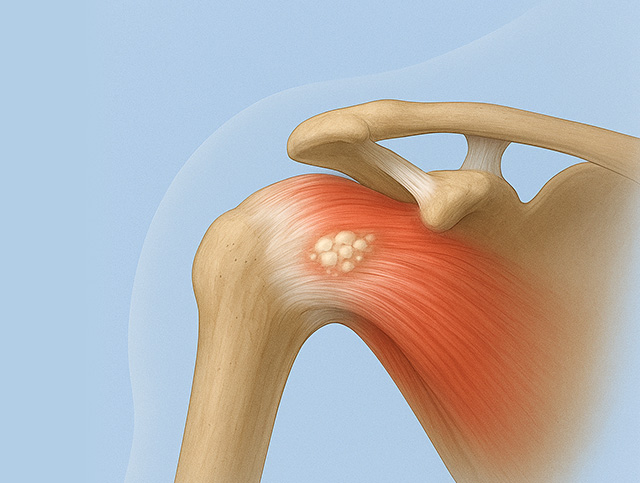

석회화건염

어깨 힘줄의 손상으로 인한 퇴행성 변화와 혈액순환 장애로

이 부위에 칼슘이 쌓이면서 석회 침착이 발생

갑작스러운 극심한 통증과 시간이 지나면서 완화되는 증상 반복